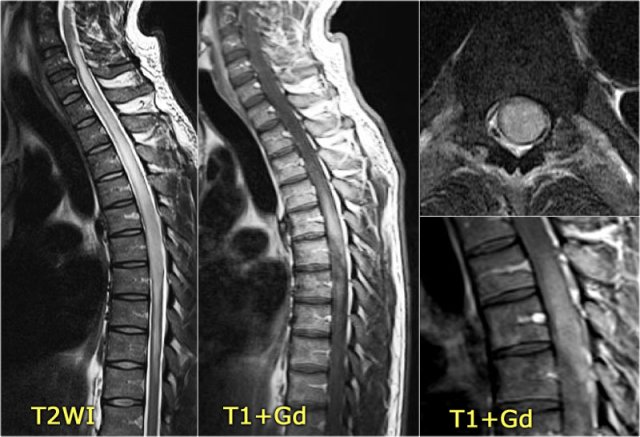

On the left images of a child who presented with unilateral neuritis optica.

Images of the brain were otherwise normal.

Continue with MRI of the spine.

Patients who have one episode of optic neuritis or myelitis and who test positive for NMO-IgG are at high risk for developing the full spectrum of NMO.

One month later this child presented with acute transverse myelopathy, i.e. bilateral symptoms.

The images show abnormal signal in the spinal cord with swelling and some enhancement.

An astrocytoma could very well present with these images, but given the history of an optic neuritis and the acute myelopathy, we do not think of a tumor.

This proved to be NMO and the Ig-test for NMO was positive.

In the original description of Devic's disease the optic neuritis and the myelopathy were simultaneously, but now we know that this is not always the case.